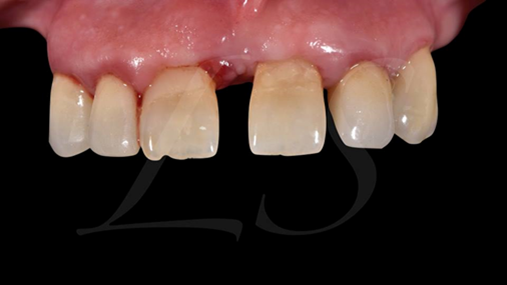

Clinical case: Full-arch implant treatment with immediate loading & extraction implantation

- Courtesy of Dr. Laurent Sers, France -

AnyRidge, R2GATE, guided surgery, Dr. Laurent Sers, immediate loading, maxilla

AnyRidge implant system, R2GATE, Digital prosthesis